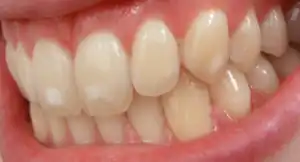

It appears as a range of visual changes in enamel[4] causing degrees of intrinsic tooth discoloration, and, in some cases, physical damage to the teeth. The severity of the condition is dependent on the dose, duration, and age of the individual during the exposure.[1] The "very mild" (and most common) form of fluorosis, is characterized by small, opaque, "paper white" areas scattered irregularly over the tooth, covering less than 25% of the tooth surface. In the "mild" form of the disease, these mottled patches can involve up to half of the surface area of the teeth. When fluorosis is moderate, all of the surfaces of the teeth are mottled and teeth may be ground down and brown stains frequently "disfigure" the teeth. Severe fluorosis is characterized by brown discoloration and discrete or confluent pitting; brown stains are widespread and teeth often present a corroded-looking appearance.[1]

| Normal | 0 | The enamel represents the usual translucent semivitriform (glass-like) type of structure. The surface is smooth, glossy and usually of pale creamy white color |